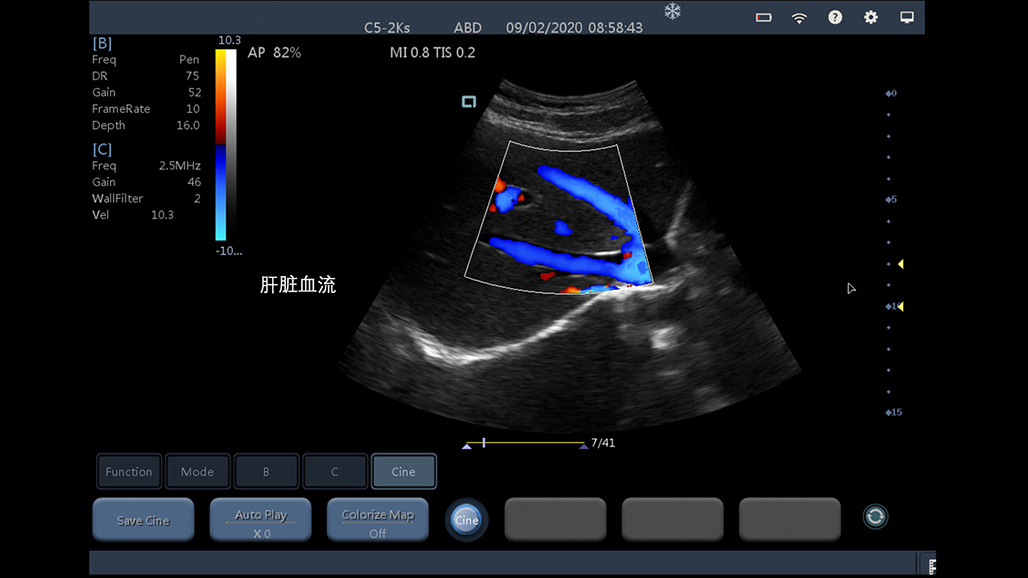

腹部

肾脏

妇科产科

心脏

肺等